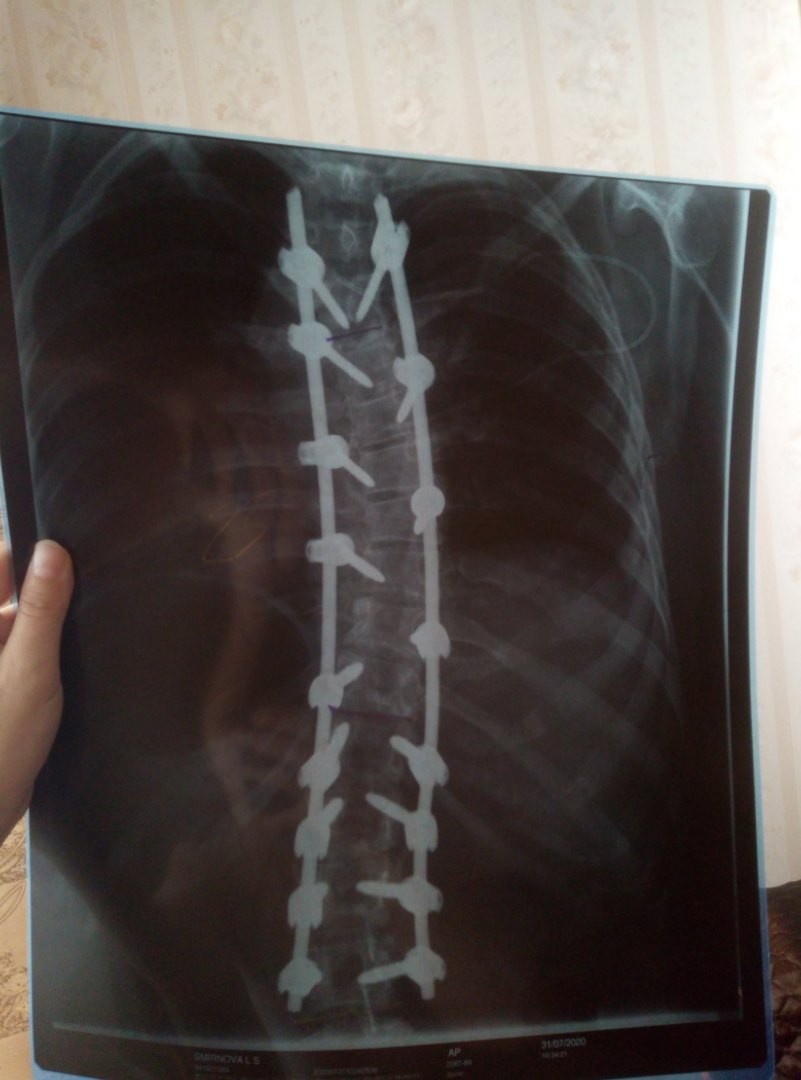

Кстати, вот мои снимки после)) Слабонервным не смотреть))

градусы исправили очень хорошо!

Устрошающе, не правда ли?)) Первый мой вопрос был- куда эти шурупы прячутся в организме)))